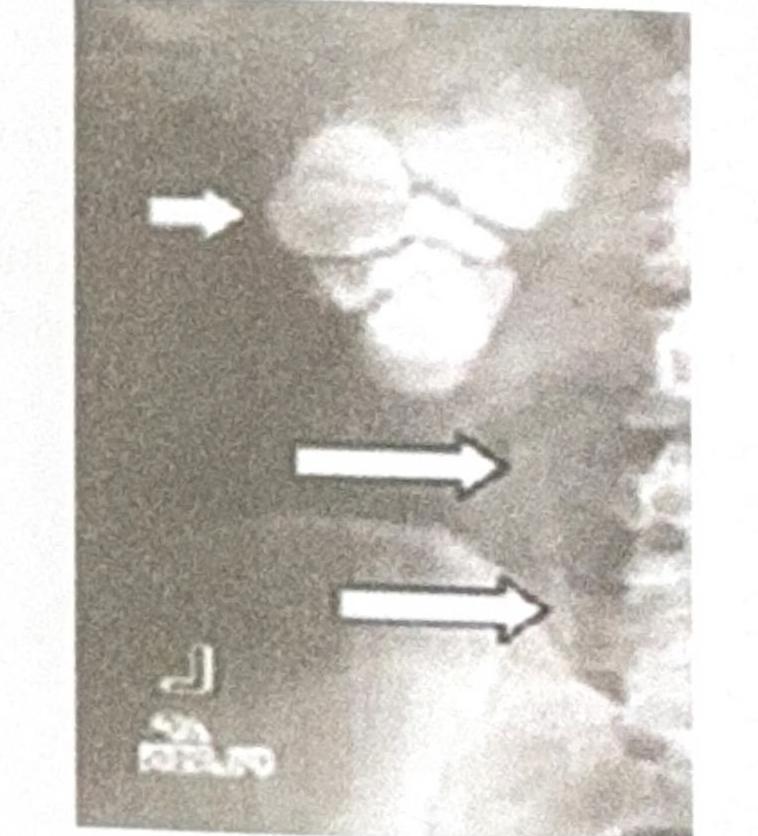

A 30-year-old female presents with sterile pyuria. The radiograph below is provided. What is the most likely diagnosis?

Explanation: ***Putty Kidney*** - The image visible in the question shows a **caseous calcification** of the renal parenchyma, which is characteristic of a "putty kidney," a late manifestation of **renal tuberculosis**. - **Sterile pyuria** is commonly associated with renal tuberculosis, where Mycobacterium tuberculosis infection leads to chronic inflammation and granuloma formation in the kidney, eventually resulting in caseous necrosis and calcification. *Psoas Calcification* - This typically refers to calcification within the **psoas muscle**, which would appear as a linear or amorphous calcification along the path of the muscle, an appearance not consistent with the image. - While psoas abscesses can calcify, they would not manifest as widespread renal parenchymal calcification and are not specifically linked to sterile pyuria in this manner. *Staghorn Calculus* - A **staghorn calculus** is a large, branched kidney stone that fills all or part of the renal pelvis and calyces, resembling the antlers of a stag. - While these stones are composed of mineral salts and would be radiopaque, their morphology is distinctly different from the diffuse, caseous calcification seen in the image. *Nephrocalcinosis* - **Nephrocalcinosis** is a condition characterized by diffuse microcalcifications throughout the renal parenchyma, usually affecting the tubules. - The calcifications in the provided image appear more nodular and clustered, consistent with late-stage tuberculous caseous necrosis, rather than the fine, diffuse pattern of nephrocalcinosis.